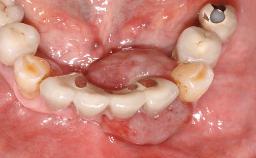

Recurrent Peri-implantitis Leading to Implant Removal

A 65-year-old female patient was referred to the periodontist for assessment and management of implant site 12. Implant 12 had been placed ten years previously and restored with a cemented single crown. The patient was a non-smoker in good general and periodontal health. On examination there were 7 mm probing depths at implant 12 with suppuration and bleeding on probing. The patient was aware of the presence of pus but had no discomfort. A periapical radiograph showed marginal bone loss to approximately the third thread of the implant. Previous radiographs obtained from the referring clinician indicated that there had been progressive bone loss since the implant was restored. A diagnosis of periimplantitis was made.